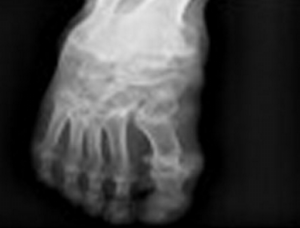

腳部易發痛風嗎,吃什么藥治療痛風?

由于尿酸升高沒法正常排出體外堆積在關節處久而久之容易發作痛風,大部分人都是腳部易發痛風嗎?痛風發作的時候能吃優立通治療嗎?優立通治療痛風的效果好不好呢?

痛風發作的癥狀表現有以下特點:突發性:痛風在發作之前一般沒有任何癥狀,主要在夜間發作,患者一般會被突然的關節疼痛所驚醒。疼痛難忍:痛風發作時,疼痛感特別強,那種疼痛呈“刀割樣”、“咬噬樣”或“燒灼樣”劇烈,多數患者無法忍受這種痛苦。發作主要集中在腳部關節,突然間出現大腳趾、腳踝、膝關節,或者下肢某個大關節腫疼。最典型的例子是前一天晚上聚會、喝酒,第二天凌晨疼醒,往往是吃點止疼藥,忍到第二天去痛風??瓶床 C看渭毙园l作時間約1周,其后自然緩解,但是痛風會反復發作,痛風反復發作可導致發作關節增多,影響正常的活動。